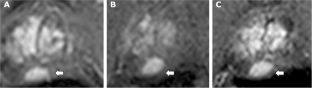

Multiparametric magnetic resonance imaging (mpMRI) is being used increasingly in the setting of active surveillance (AS) for prostate cancer. We investigated changes in the mpMRI appearance of lesions on AS, to show the variability of volume measurements in visible lesions and assess change in lesion size according to grade.

43/86 men did not have a visible lesion on the initial mpMRI (≤2/5). Of these, 5/43 had developed a lesion scoring ≥3/5 at a median of 3.6 years of follow up. 40/86 had a lesion scoring ≥3/5 on two or more scans. There was a significant increase in volume over 3.6 years by a median of 10% (p < 0.01)–by a median of 6% for Gleason 3+3 and 18% for 3+4 (p = 0.058). Thirty-five men had a visible lesion on two scans separated by <2 years; of these, 21/35 showed a 78% median increase in tumour size between the two scans and 11/35 showed an apparent 25% median decrease in lesion size.

A total of 17% of men with no visible lesion developed a visible lesion at a median follow up of 3.6 years. It is possible to show significant growth in patients with a visible lesion, but variability in volume measurements between scans means that it is difficult to reliably detect increases of this order. This variability may inform the design of mpMRI protocols in AS and the time between follow up scans.